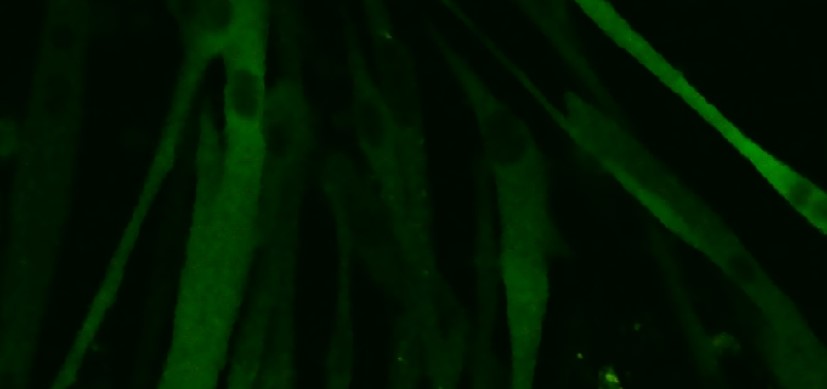

Schwann cells modulate nociception in neurofibromatosis 1: buff.ly/3UwBPfJ @CincyChildrens #Neuroscience

Congrats to @NamrataGRRaut on her newest publication looking at a novel mechanism of pain development in neurofibromatosis 1! insight.jci.org/articles/view/…